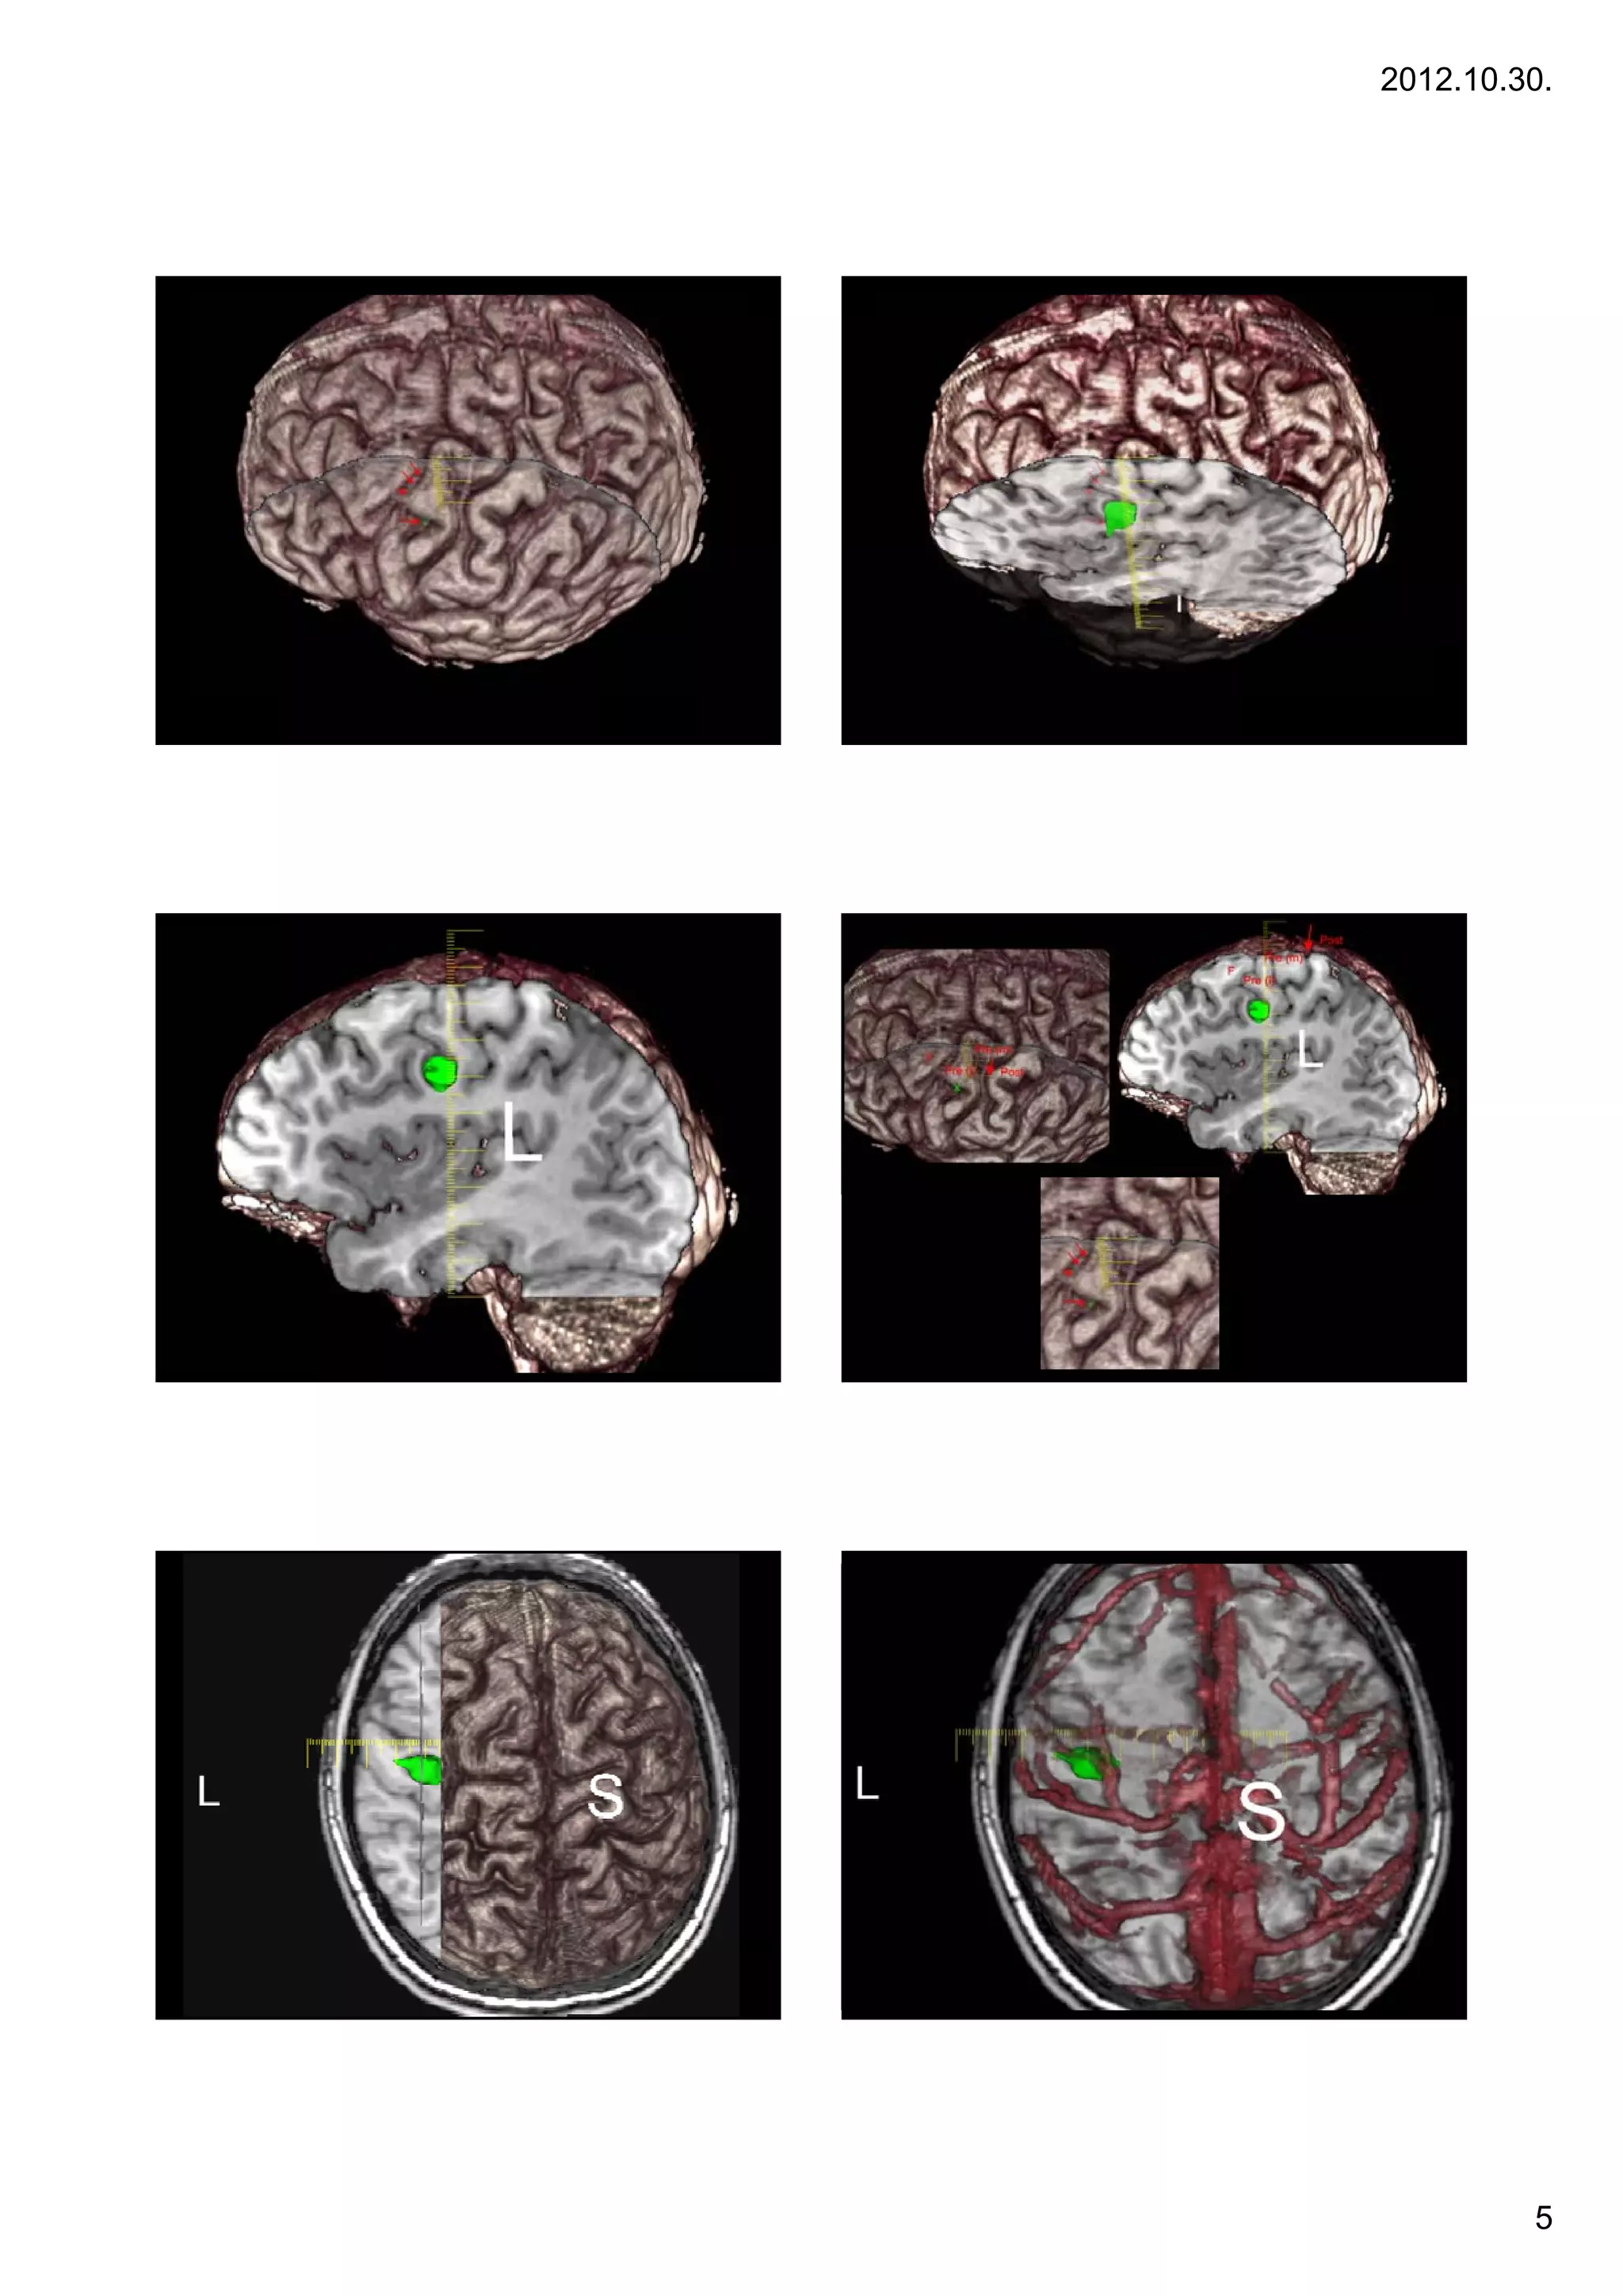

Summary – multimodality in

neurosurgery

• Locate anatomy

• Locate vessels

• Locate eloquent (neighbouring) areas

•LLocate white matter t t

t    hit    tt tracts                                              Case 1

1.

• Locate functional domains

• Plan treatment